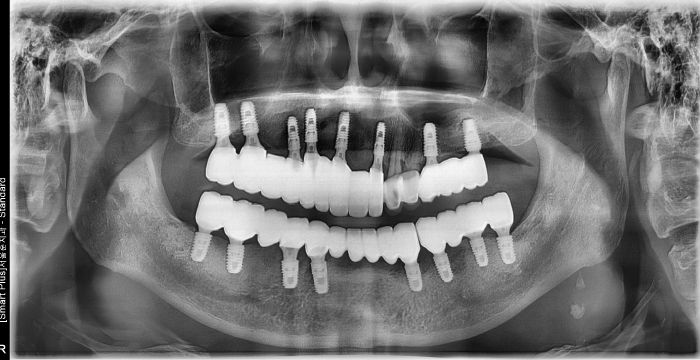

무치악 임플란트도 즉시 식립 임플란트로!

치아가 모두 상실된 경우 그냥 방치하게 된다면 잇몸뼈(치조골)가 계속 소실됩니다. 서울바른훈치과의 무치악임플란트는 다년간의 임상경험이 풍부한 서울대출신의 의료진이 직접 시술은 물론 자체 디지털 기공실 협진 시스템을 갖추고 있습니다.

즉시 식립 임플란트 전후 사례

• 식립 전

식립 후